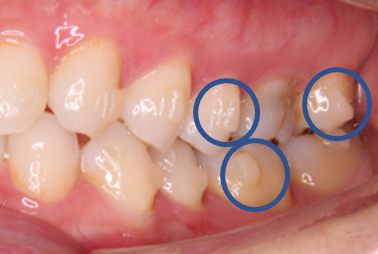

インビザライン矯正を実際にスタートするにあたり、まず行うこととして、アタッチメントと呼ばれる歯の表面にレジンの突起物を付けます。

これを付けることで、歯に加わる力を調整し、歯を効率的に動かすことができます。

アタッチメントには、実は様々な形状があり、歯を動かしたい場所や動かし方によって、形状、数、場所が変わってきます。

どこの場所にどのような形のアタッチメントを付けると、効率よく歯が動かせるのか、とても考えられているんです(*^^)v

しかも、白色なのでよく見ないと付いているのかもわからない程度で、

実際にアタッチメントを付けてもらうと、装着時はまったく痛みもなく、行うことができました!!

写真で見ると、こんな感じです↓↓↓